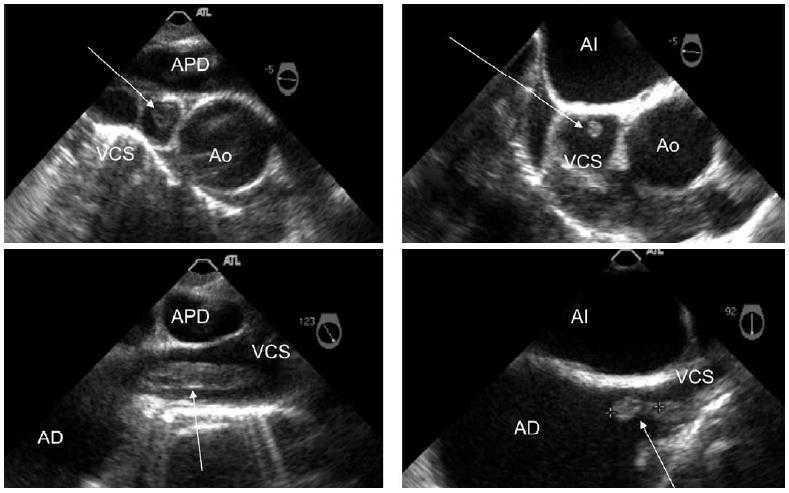

Figura 1. Estudio transesofagico

La paciente consulta por síndrome febril sin otro foco infeccioso que el catéter. Se inició antibioterapia y se procedió a la retirada del catéter, remitiendo la fiebre en veinticuatro horas. Una semana más tarde reaparece el cuadro febril. Se le realizó un ecocardiograma transesofágico para descartar una endocarditis, evidenciándose la presencia de un trombo en el trayecto de la vena cava superior que se introducía un centímetro en la aurícula derecha. Ante estos hallazgos se inició anticoagulación y antibioterapia sistémica, pero cinco días más tarde la paciente persistía con fiebre y clínica bacteriémica, por lo que se decide la extracción quirúrgica del trombo. La intervención implicó circulación extracorpórea, apertura de la aurícula derecha y venotomía de la vena cava superior, con extracción del trombo. Tras la cirugía la paciente ha permanecido estable clínicamente sin nuevos episodios febriles.